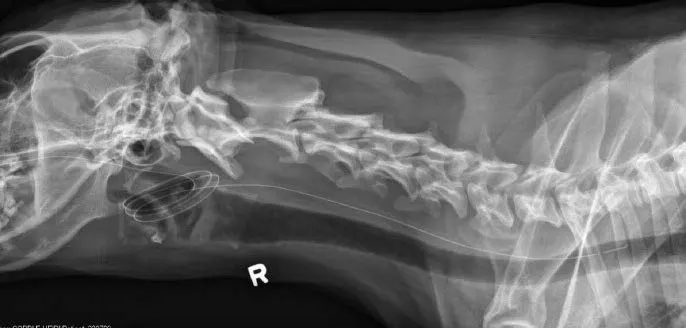

Another quick way to assess placement is to attach the tube end to an airway gas analyzer (eg, capnograph). When the tube end is located in the esophagus or stomach, there is no capnographic waveform, respiratory rate, or end-tidal CO2 detectable by the machine, which sets off its apnea alarm.6 End-tidal CO2 and respiratory rate are both measureable, and a capnographic wave-form is elicited if the tube end is in the trachea, nasopharynx, or nasal cavity. Because an NE or NG tube could be coiled in the nasopharynx (Figure 3) or kinked and still terminate in the esophagus or stomach, survey or contrast radiography is recommended to verify placement. Use of a hyperosmolar, ionic iodinated contrast medium (eg, diatrizoic acid [Hypaque]) should be avoided, as its use in a tube improperly placed in the lungs can result in inflammatory reactions and pulmonary edema.

Although this tube terminates in the esophagus, tube coiling in the nasopharynx and oropharynx will likely cause coughing or vomiting and subsequent oral expulsion of the tube end.